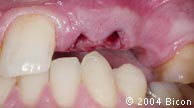

66. | 用金色的5.0mm龈沟绞刀清除任何会影响一体化基台冠完全就位的软硬组织。 |

67. | 试戴一体化基台冠,确定其是否合适。 |